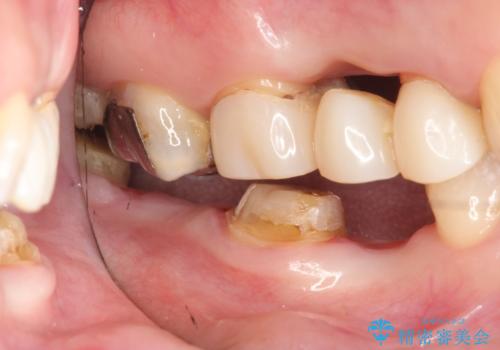

オールセラミッククラウンについて

今回用いたオールセラミッククラウンはジルコニアフレームという白い素材の上にセラミックを盛っているため、審美性が非常に高いのが特徴です。

また、ジルコニアは人工ダイヤモンドの材料にも使われているほど高い強度を持っており、そのためオールセラミッククラウンは審美性だけでなく、奥歯やブリッジの補綴も可能とするクラウンです。